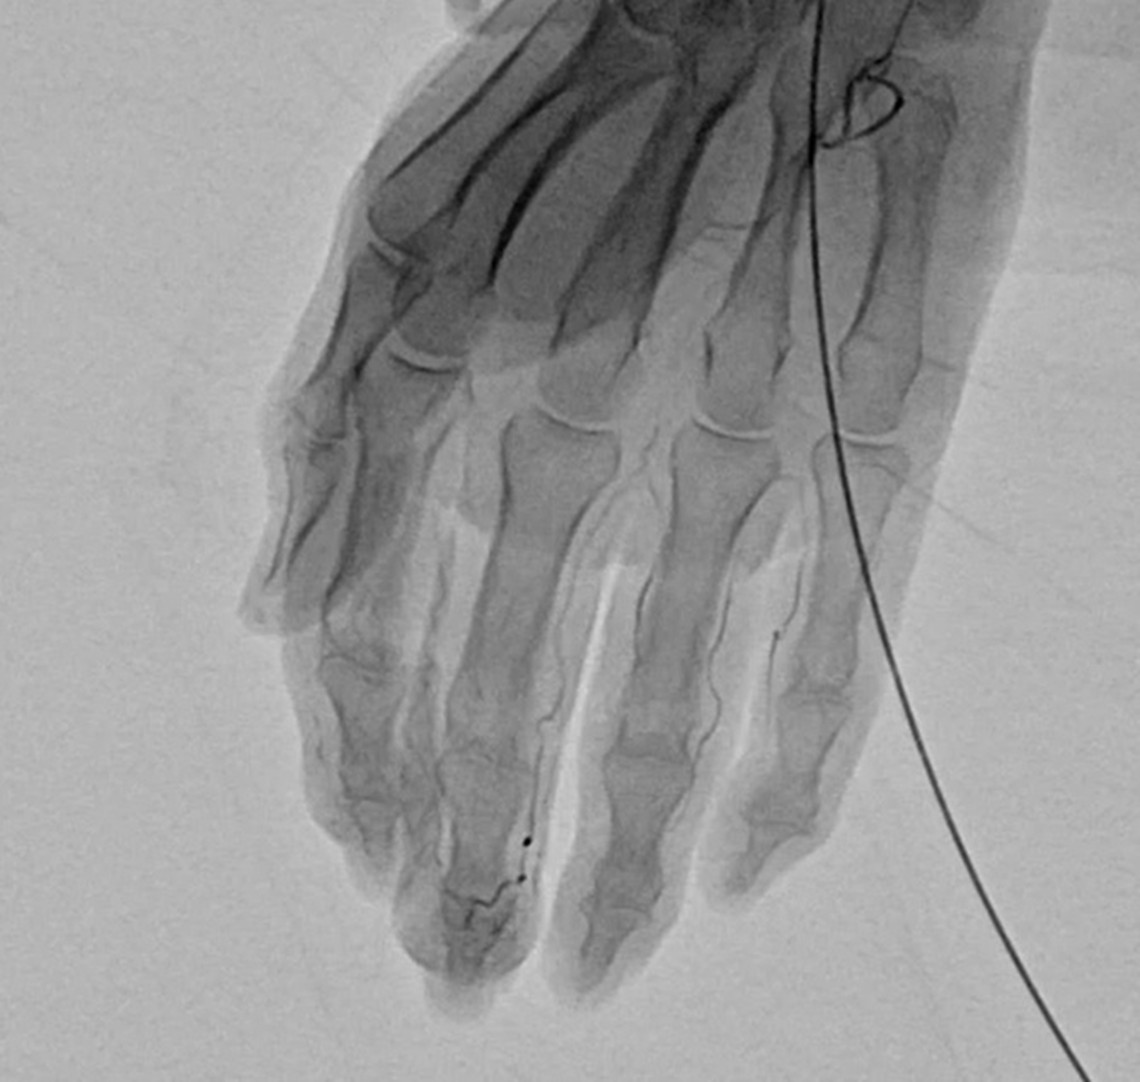

慢性的な痛みが続く部位には、異常な毛細血管(新生血管)=「モヤモヤ血管」が発生していることがあります。これは炎症や組織のダメージにより、けがや炎症が起きた場所の組織を修復しようとして、本来はないはずの場所に過剰に増えてしまった毛細血管です。画像検査で霧がかかったように見えることから「モヤモヤ血管」と呼ばれます。

血管の中に特殊な薬剤を注射して、異常な血管を塞いだり、消滅させることによって、痛みの根本的な治療をはかります。

細い針もしくは留置針をエコーで確認しながら動脈に挿入していきます。

痛みのある部分によって効果は少し異なりますが、手の動注治療では約7割の方が、痛みが半分以下になったと答え、何らかの効果を実感される方は9割以上です。治療効果は、当日あるいは数日で感じられる場合もありますが、治療後3~4週後に実感されることが多いようです。1度の治療で不十分な場合、2~3回目の治療を行うことも可能です。